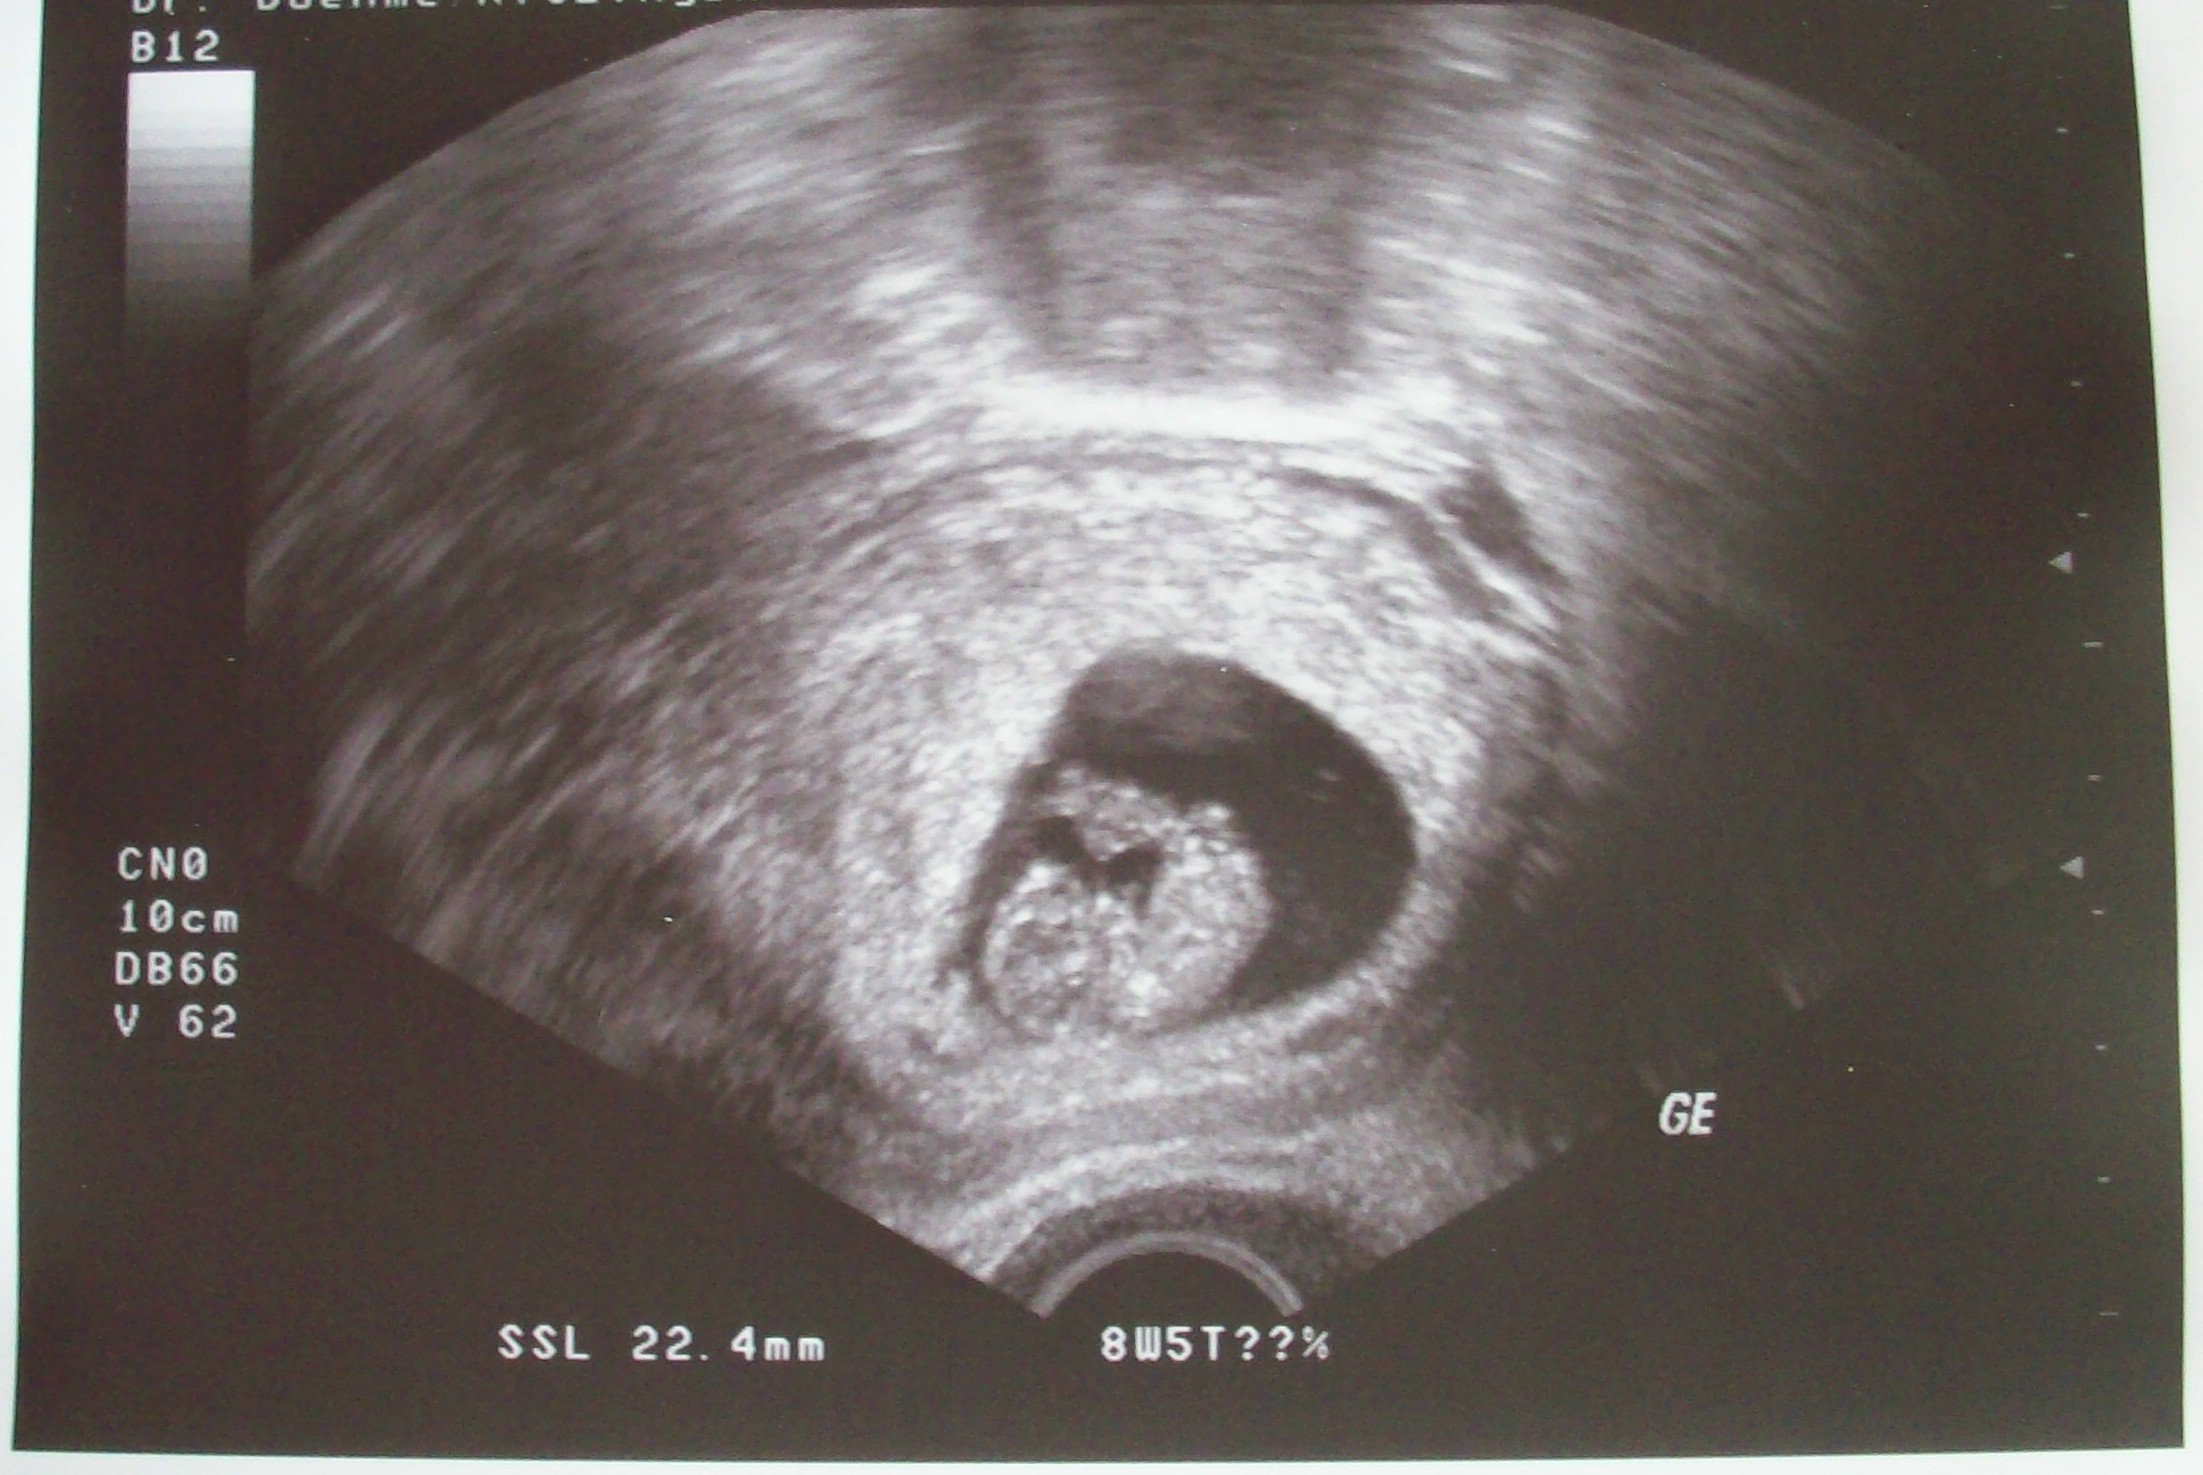

Waren vorgestern auch wieder beim US. Das Würmchen ist jetzt 22,4 mm groß, es ist alles in Ordnung ung zeitgerecht entwickelt. Den nächsten US habe ich dann in 3 Wochen. Wollt ihr vielleicht ein Bildchen sehen??